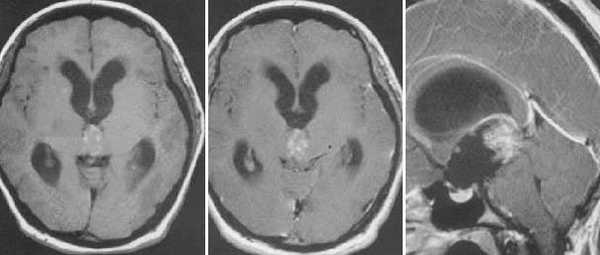

Пиллоидная астроцитома задних отделов III желудочка. Определяется небольших размеров образование с развитием окклюзионной гидроцефалии. Опухоль практически не отличается по сигналам от вещества головного мозга. После в/в контрастирование отмечается усиление МР-сигнала от образование, что позволяет уточнить расположение опухоли, степень компрессии четверохолмной пластинки и водопровода мозга.

Глиобластома зрительного бугра справа. До и после в/в контрастирования определяется объемное образование с некротическим центром и контрастируемой периферической инфильтративной частью. Деформированы задние отделы III желудочка, начальный проявления окклюзионной гидроцефалии.

Эпендимома задних отделов III желудочка. Определяется объемное образование в задних отделах шишковидной железы. Передние бугорки четверохолмия оттеснены вниз. Водопровод мозга сдавлен.

Киста эпифиза. Компрессия четверохолмной пластинки и частичное сдавление водопровода мозга.